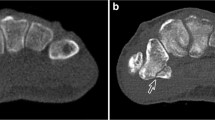

Obtained 3D models were imported into 3-matic Research (V 13.0, Materialise NV, Leuven, Belgium). Next, models generated from CT image series (in following: CT-models) were registered onto the surface scan models with a “3-point registration”, selecting the dorsal tubercle, the styloid process, and the most proximal point of the interosseous margin. For convergence of registration, a “global registration” algorithm was executed additionally (distance threshold: 1.000, 20 iterations, sample percentage 100). Analogue to the models generated from the surface scans, the epoxy glass wedge was removed manually, thus, splitting the radius models into the epiphysis and diaphysis. Separate evaluations for the epiphysis and diaphysis were performed since it was recognized in a pilot trial that the segmented SAT models show a clear dimensional overestimation in the diaphysis, but not as pronounced in the epiphysis. Further, the fracture line was superimposed with the transition region of the epiphyseal and diaphyseal region in the MMT algorithm, making the splitting in these two regions even more intuitive. For both regions, a “part comparison analysis” (signed) was performed for each CT-model, with respect to the corresponding surface scan model (see Fig. 3). The density distribution histograms were exported as text files and evaluated with a customized Python script in Spyder (4.2.5, Pyhton 3.8, The Scientific Python Development Environment). Hereby, the minimum (Min), maximum (Max), first quartile (Q1), median, third quartile (Q3), interquartile range (IQR), mean, standard deviation (std), and root mean square error (RMSE) were computed. Also, density distribution histograms, probability density functions (pdf, calculated with a kernel-density estimate using Gaussian kernels), and boxplots were plotted for data visualization.

Part comparison analysis (PCA): The epoxy glass wedge is removed from the surface scan model, splitting radii into epiphysis and diaphysis. CT-models are registered onto surface scan models and PCA is performed for both regions separately, reported as histograms and boxplots (Q1: 1st quartile, Q3: 3rd quartile, IQR: inter-quartile range). Inset (Min-Max): Demonstration of elevated minimum (missing regions in CT-based 3D models) and maximum areas (overestimation in CT-based 3D models)

The current study investigated the effect of different CT technologies, methodologies and settings of image acquisition, image segmentation, and 3D model generation on dimensional accuracy of a specific bone fracture model. An established workflow was presented, whereby all mentioned sources of errors were analyzed separately. Mean absolute dimensional deviation ranged from 0.03 mm (epiphysis, NAEOTOM Alpha, optimized protocol) to 0.32 mm (diaphysis, Brilliance 64 scanner). These deviations can be queued in the lower half of previously reported values ranging from 0.13 to 0.62 mm [24, 30, 31, 43,44,45], however, this is the first study that reported the use of PCD-CT for bone fracture modelling. In a previous study on sheep femora [28], also a Brilliance 64 EID-CT was used to obtain 3D models with a global segmentation threshold, reporting a mean deviation of 0.24 mm. The slightly lower deviation in that study might be attributed to the higher tube voltage (140 kVp vs. 120 kVp), smaller slice spacing (0.50 mm vs. 0.67 mm), and different skeletal region (femora vs. radii). In the present study, the superior performance of the NAEOTOM Alpha PCD-CT and SOMATOM Force EID-CT was also reflected in a less frequent need to manually edit connected regions of bone tissue, e.g., of radius and carpal bones or skin. In general, the necessity for manual processing has been reported frequently [24, 43, 46] and highlights the necessary awareness of potential error sources generated already during image acquisition [47]. It should be noted that the maximum and minimum deviations across all CT scanners were mostly in the range of − 1.00 and 1.00 mm, indicating not only sufficient accuracy but also precision in representing the true geometric dimensions. Higher deviations were only visible in a few samples, caused by missed hole-like structures and overestimation of peak-like structures in the epiphysis (see inset Min-Max in Fig. 3). These issues are likely caused by the filling process during image processing, in combination with the partial loss of trabecular structures during the maceration process. Hence, it is assumed that these extreme values would be lower in clinical routine. Nevertheless, a visual evaluation by a radiologist or an experienced operator for the contour of the epiphysis in final models is recommended.